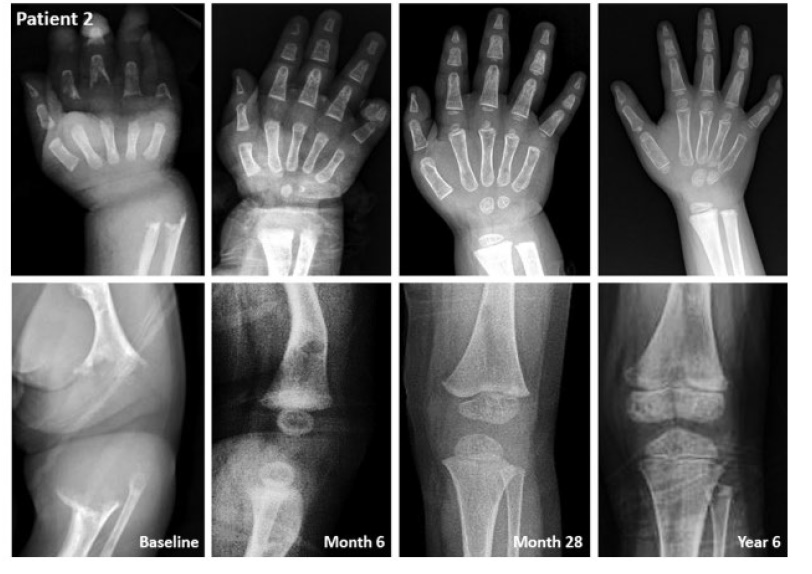

"현재 8살로 건강하게 잘 지내고 있다. 초반에는 호흡이나 섭식에 문제가 있어 인공호흡기와 위루관에 의지했는데, 치료제 덕분에 지금은 자가호흡도 가능하고 식사도 스스로 할 정도로 정상적으로 회복했다. 키나 체중도 조금씩 늘고 있다. 최근 아이가 본인 스스로 활동이 가능해지면서 조금 과격하게 활동을 하다가 골절을 경험했는데 금방 회복해서 퇴원했다. 혈액검사 수치나 X-ray상에서도 좋아진 것이 확연하다."

- 정상 체중으로 태어났으나, 생후 6주 차에 성장, 섭식 문제로 첫 내원

- 구루병 소견, 낮은 ALP로 HPP 의심하여 ALPL 유전자 검사를 통해 HPP 확진함

- 생후 21개월에 스트렌식 치료를 시작함

- 치료 통해 ALP 수치는 크게 증가, PLP 수치는 감소함

- 치료 4.5년 후 인공호흡기 사용 중단

- 최근 외래에서 무릎을 꿇고 균형을 잡을 수 있게 된 점을 확인함